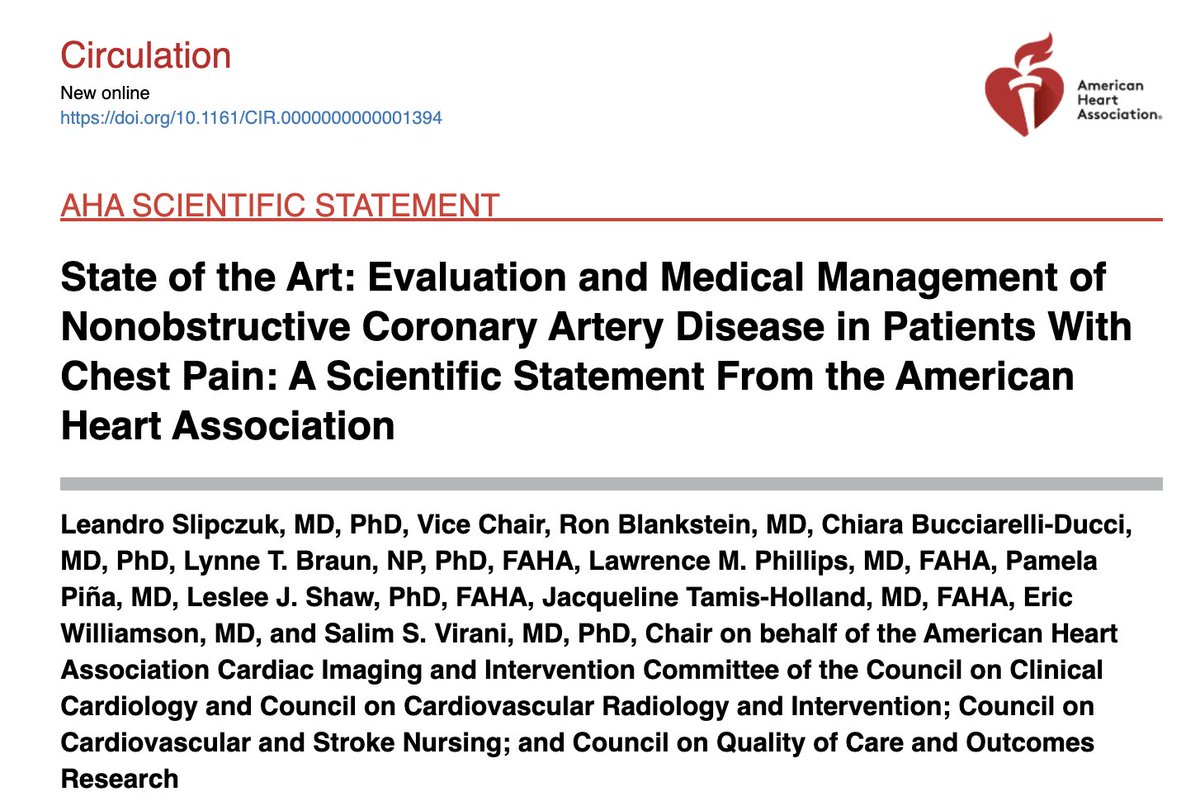

🔴State of the Art: Evaluation & Medical Management of Nonobstructive Coronary Artery Disease in Patients With Chest Pain: A Scientific Statement @CircAHA #Cardiology #CardioEd #FOAMed #AHA2025